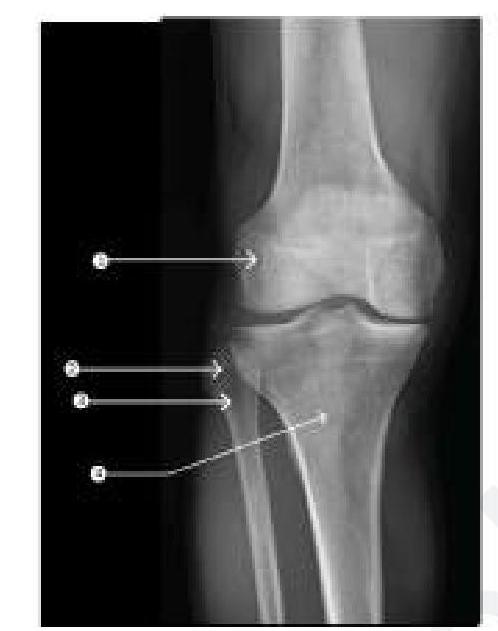

Surgery was performed as shown in the image below. What is the name of the procedure?

Explanation: ***Chopart amputation*** - The image shows a disarticulation through the **talonavicular and calcaneocuboid joints**, which defines a **Chopart amputation**. - This procedure removes the distal foot while preserving the **calcaneus and talus**, forming a stump that allows for some ankle motion. *Below knee amputation* - A below-knee amputation involves transection of the tibia and fibula, preserving the knee joint, which is much more proximal than shown in the image. - This type of amputation removes a significant portion of the lower leg, with the foot entirely removed, unlike the partial foot amputation depicted. *Above knee amputation* - An above-knee amputation involves disarticulation or transection through the femur, completely removing the lower leg and knee joint. - This is a much more extensive amputation than what is illustrated, which is confined to the foot. *Lisfranc amputation* - A Lisfranc amputation is a disarticulation through the **tarsometatarsal joints**, removing the metatarsals and phalanges but preserving the tarsal bones. - The image clearly shows the incision more proximally, at the midtarsal level, specifically through the talonavicular and calcaneocuboid joints, not the tarsometatarsal joints.